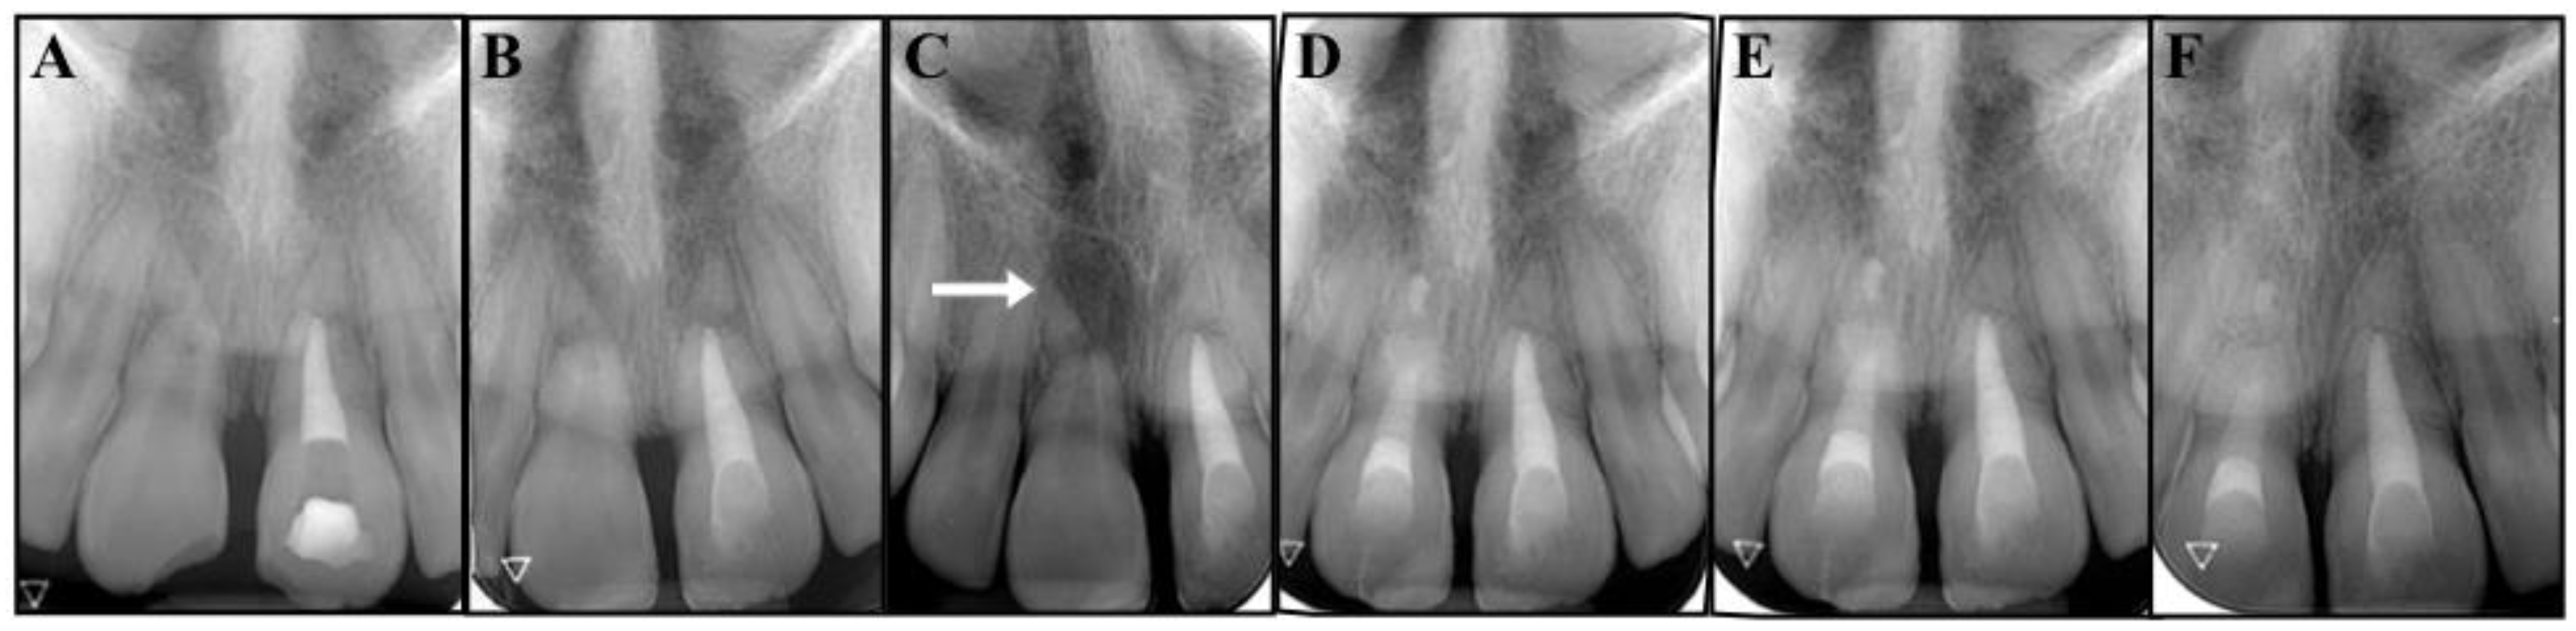

After the administration of local anesthesia, a rubber dam was put in place, and a standard access cavity was opened to perform the endodontic treatment on tooth #2.1 (Figure 2A). The working length was assessed with an intra-operative periapical radiograph with a #25 hand k-file, and the canal was instrumented using a sequence of hand K-files of alternating irrigation and with a copious amount of 5.25% sodium hypochlorite. The apical portion of the coronal segment of the root was examined under a Zeiss surgical microscope (Oberkochen, Germany), and the wide opening was identified as shown in Figure 2B.

Figure 2.

(A) Standard access cavity of tooth #2.1. (B) Identification of the wide opening of the apical portion of the coronal fragment of tooth #2.1 (arrowed). (C) Apical barrier of Portland cement (arrowed). (D) Complete obturation of the canal with the cement.

Upon finishing the instrumentation, calcium hydroxide was introduced as an intracanal medication for 4 weeks, and the access cavity was closed with a cotton pellet and temporary cement (Cavit, 3M ESPE, St. Paul, MN, USA). The tooth was asymptomatic during the postoperative period.

At the second appointment, the temporary filling was assessed as intact, the procedure was repeated, the calcium hydroxide was removed, and the canal was filled with Portland cement (ProRoot MTA, Dentsply Tulsa Dental, Tulsa, OK, USA) (Figure 2C,D) [16,17,18]. The cement was prepared according to the manufacturer’s instructions, carried into the canal with the MAP System (MicroApical Placement Dentsply, Maillefer, Switzerland) and condensed with hand pluggers. The access cavity was sealed with a composite bonded restoration [19]. Two class IV restorations were further performed on the fractured coronal segments of teeth #1.1 and #2.1, using composite and dental adhesive (Figure 3B).